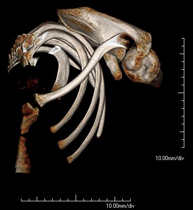

- Shoulder CT

Radiological examination based on an X-ray system and detectors that rotate around the patient, reconstructing the images by computer (multidetector computed tomography - MDCT) to study the bones, muscles and joints of the shoulder.